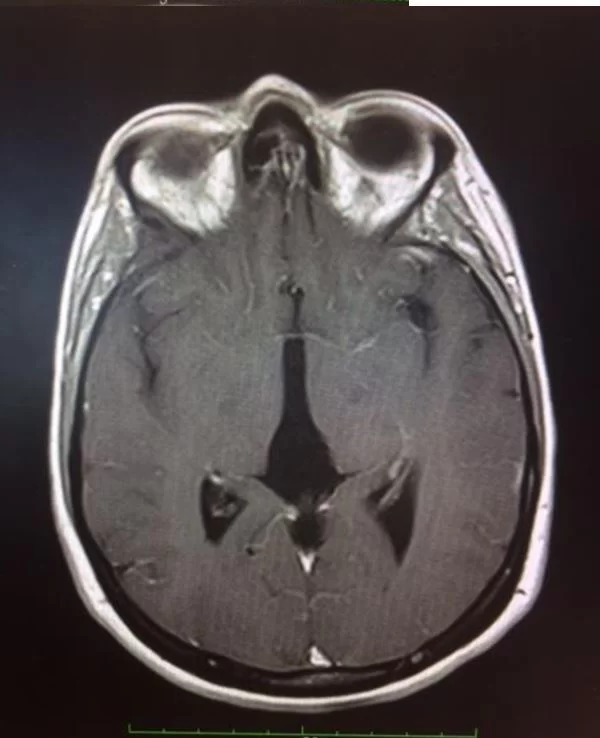

Η μετεγχειρητική αξονική τομογραφία εγκεφάλου δείχνει πλήρη αφαίρεση της βλάβης. Η ιστολογική εξέταση ανέδειξε πινεαλοκύττωμα (WHO I).

Μετεγχειρητικά η ασθενής παρουσίασε σύνδρομο Parinaud το οποίο υφέθη πλήρως εντός 12 μηνών και η ασθενής επέστρεψε στην εργασία της ως βρεφονηπιοκόμος.